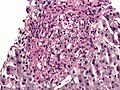

Microscopic

Features:

- Often in yeast form - in tissue, spherical, 2-5 micrometres.[9]

- Intracellular[10] - may be within macrophages that form a granuloma.

- Nice bright red on PAS-D.

- Have a "central dot".[11]